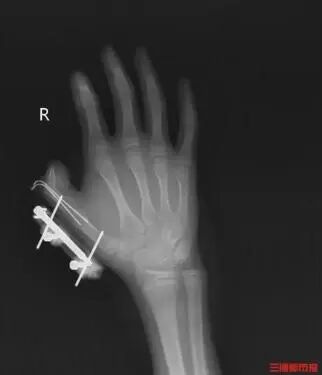

2025年8月,湖南一名14岁的少年在网购冰淇淋的箱子里发现了用于冷藏的干冰,便拿走当成玩具玩,捏在手里反复摇晃。突然,密封袋里的干冰发生爆炸。

2024年9月,山东济南,一名8岁男孩将干冰塞到小瓶口的玻璃瓶里,由于不停摇晃,压力急剧增大,玻璃瓶突然爆炸,飞溅的碎玻璃扎进其左脸、头部、耳部及颈部血管,大大小小约30处伤口。

5.若被干冰冻伤或炸伤应立即就医。